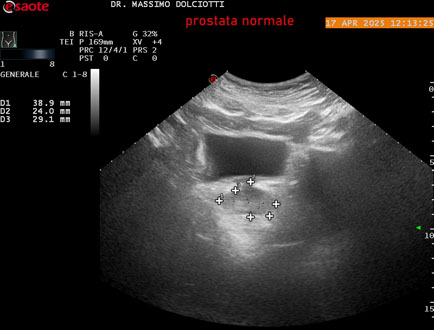

Data inserimento: 01/10/2025

Ecografia del: 17/04/2025

Strumento: Esaote MyLab Eight

Sonda: Convex Multifrequenza 1-8 MHz, Endocavitaria Multifrequenza 3-9 MHz e 3-13 MHz

Età Paziente: M 35 anni

Motivazione dell'esame: disuria.

Commento all'esame: le immagini ed il video documentano la prostata di ecostruttura regolare e morfovolumetria normale con diametro trasversale di 40 mm, diametro anteroposteriore di 21 mm e diametro longitudinale di 43 mm, con volume prostatico calcolato di 18 cc (v.n. < 20 cc), il profilo prostatico è regolare e netto, non si documentano calcificazioni intraghiandolari, la vascolarizzazione della ghiandola è normale. La vescicola seminale destra presenta diametro longitudinale di 44,4 x 7,8 mm, la vescicale seminale sinistra ha diametro longitudinale di 45,3 mm x 7,2 mm.

Conclusioni: prostata normale (normal prostate).